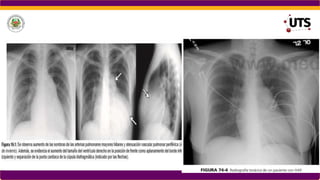

Lippincott Williams & Wilkins, 2008, chest radiology